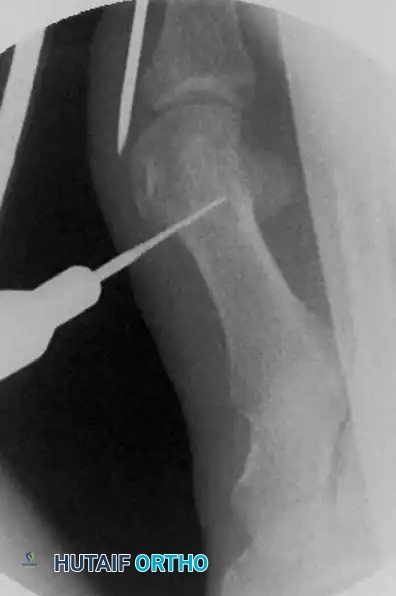

إدخال سلك التثبيت الدقيق

الخطوة الأولى تتمثل في وضع السلك المعدني الدقيق الذي سيقوم لاحقا بالتقاط وتثبيت رأس العظمة بعد قصها. يتم إدخال سلك بقطر ملليمترين بدءا من الزاوية الداخلية لظفر إصبع القدم الأكبر.

إدخال السلك المعدني الدقيق

يحرص الجراح بشدة على تجنب اختراق منبت الظفر لتفادي أي ألم أو تشوه في الظفر بعد الجراحة. يتم دفع السلك نحو الأعلى بحذر شديد. من الضروري جدا أن يمر السلك في مسار خارج غشاء العظم على طول الجانب الداخلي للإصبع. هذا المسار الدقيق هو ما يسمح لاحقا بإزاحة العظم وتصحيح التشوه.

مسار السلك المعدني خارج غشاء العظم

يتم دفع السلك حتى يستقر بقوة في الجانب الداخلي لرأس عظمة المشط. هذا التثبيت المحكم ضروري لمنع العظمة من التحرك بعشوائية بعد قصها.